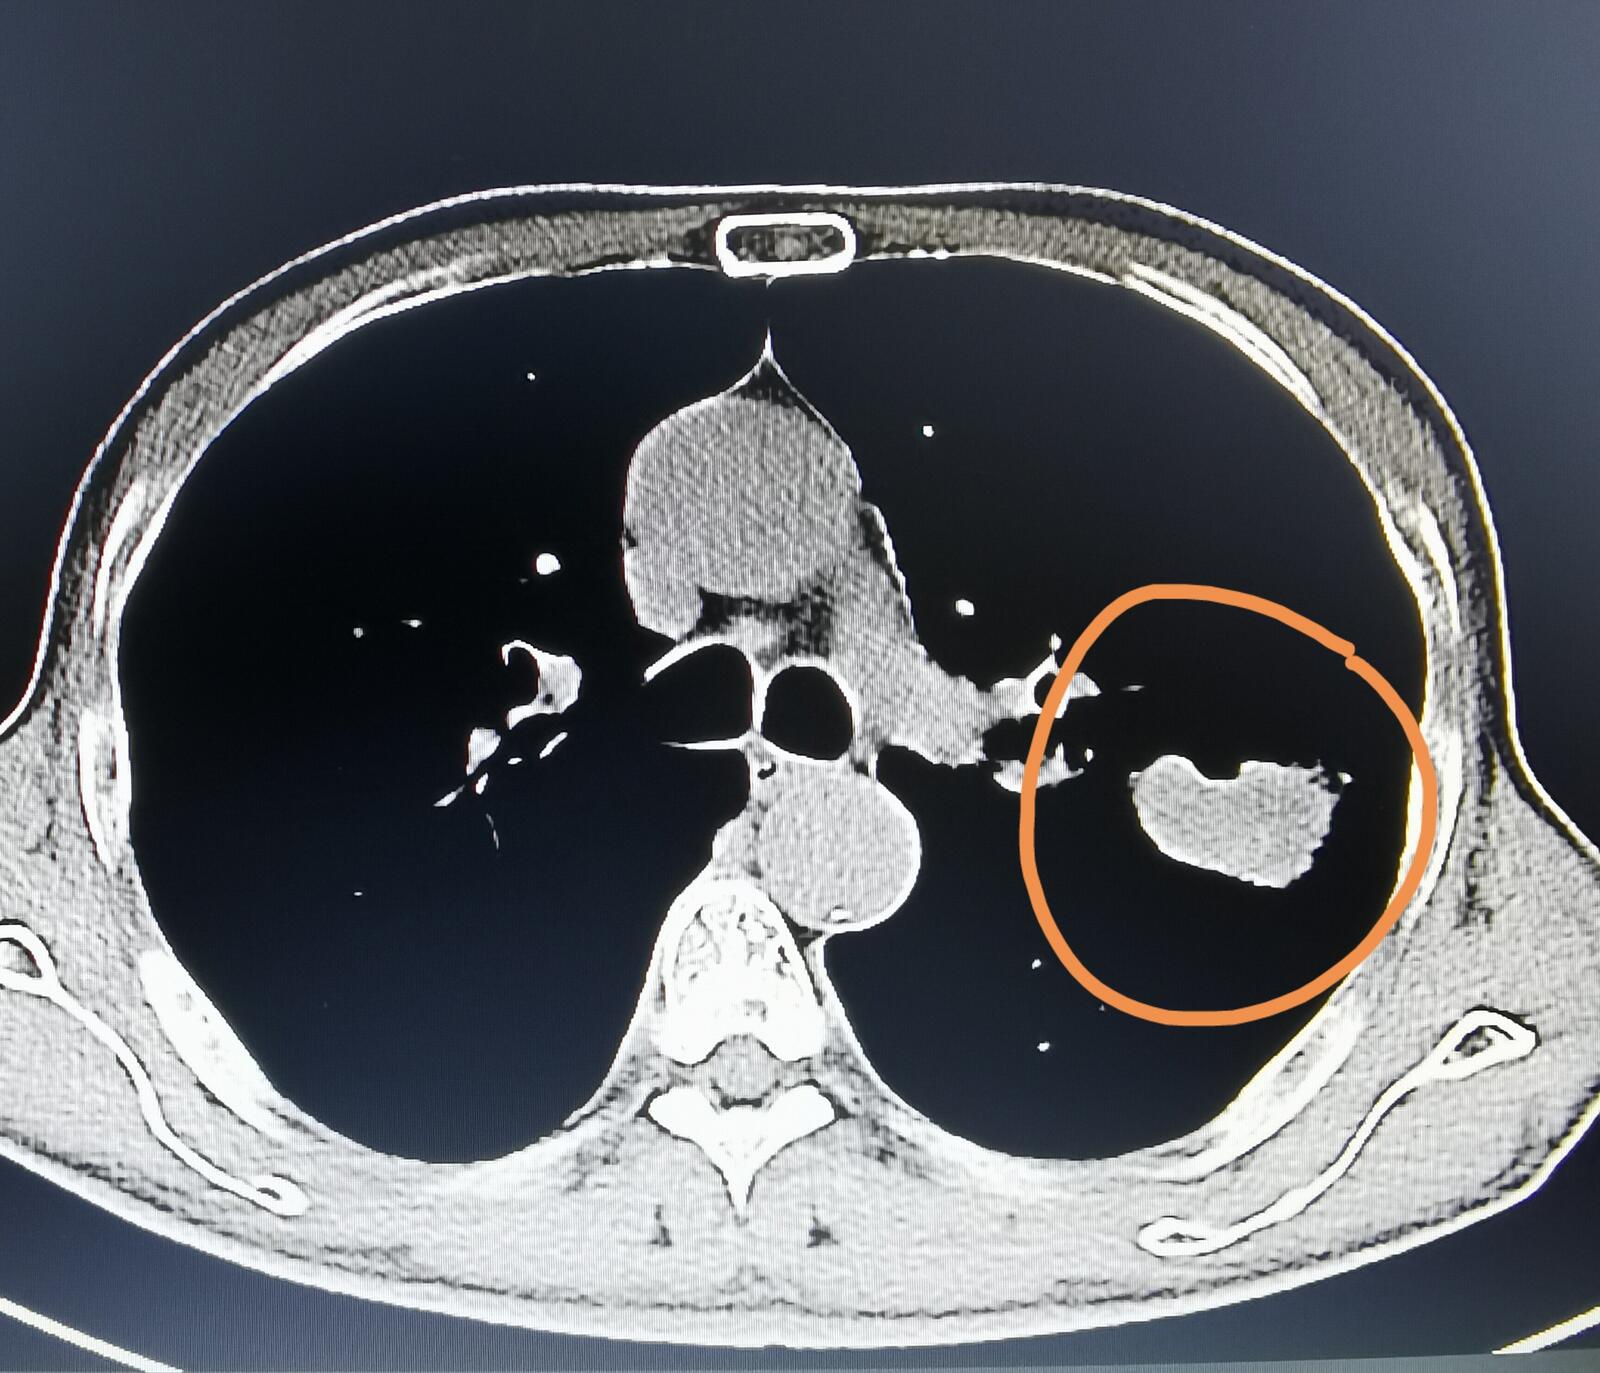

有一位家住河北省57岁的男士,近两个月来出现了上腹部疼痛,这种疼痛比较轻微,可以忍受,不是那种特别剧烈的,应该叫做隐隐作痛。刚开始的时候,他以为是胃口的问题,但后来这种感觉一直存在,他到我们医院来检查,发现了胰腺有一个占位,考虑是胰腺癌。同时一侧肾上腺和脾脏里面也都有占位,有可能是胰腺癌的转移。他在我们医院还做了一个胸部CT,结果发现了在左下肺也有一个占位。

他的儿子想知道左肺这个占位和胰腺癌有没有关系?我仔细阅读他的片子,觉得肺部这个占位恶性的可能性非常大,但考虑原发性肺癌,不太考虑胰腺癌的肺部转移。当然,最终还要以病理报告来决定到底是什么病。从他儿子那里我知道,这位患者抽了很长时间的烟,但之前从来没有做过体检,这还是他第一次做胸部CT和腹部的检查。